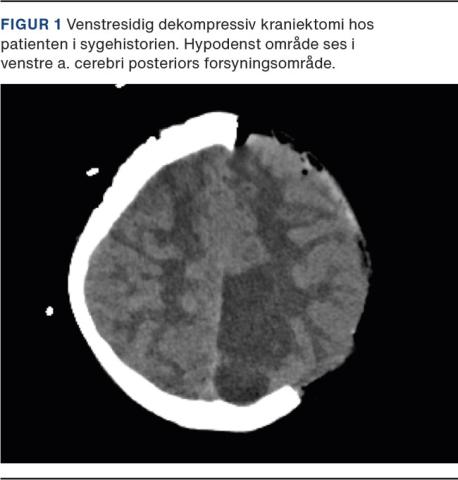

En tiårig, tidligere rask pige debuterede med opkast, konfusion og efterfølgende ukontaktbarhed og kramper. Forudgående havde hun uden sikkert debuttidspunkt gennem to uger haft ukarakteristisk hovedpine med varierende intensitet og havde bl.a. fortalt, at cykelhjelmen strammede. Kramperne blev brudt efter 75 minutter efter nasal og i.v. indgift af midazolam samt i.v. indgift af valproat. Blodprøver inklusive infektionstal var normale. Forgiftning blev udelukket efter drugscreening og blodprøver. Fortsat bevidsthedspåvirket blev patienten overflyttet til observation på et børneintensivafsnit. Seks timer efter indlæggelse blev der udført en CT af cerebrum inklusive angiosekvens, som viste subaraknoidal hæmoragi (SAH) udgående fra et aneurisme på venstre a. cerebri posterior. Patienten blev sederet og intuberet mhp. neurointervention og -monitorering. Aneurismet kunne ikke aflukkes separat fra arterien, som derfor blev okkluderet ved aneurismet. Patienten havde høje intracerebrale tryk til trods for, at der blev givet maksimalt tryksænkende behandling. På re-CT blev der observeret tiltagende cerebralt ødem på både lokal iskæmisk og global baggrund, og der blev derfor foretaget en dekompressiv kraniektomi med fjernelse af knogleplade på venstre side (Figur 1).

Der blev i denne sygehistorie udført en dekompressiv kraniektomi, men der findes kun yderst sparsom evidens omhandlende dette indgreb hos børn, hvor årsagen til forhøjet intracerebralt tryk er atraumatisk. Proceduren udføres derfor fortsat baseret på individuel vurdering.